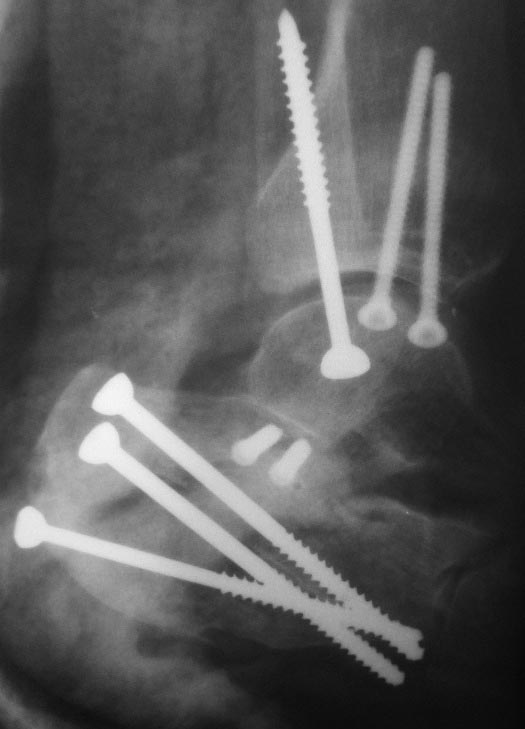

Уважаемый БЕК надеюсь я Вас не обидел. Кстати есть еще один

малоинвазивный вариант по по пяткам))